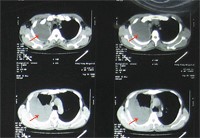

二例:患者男、24岁,一月前发现结核性胸膜炎渗出期,给予抗结核及抽水治疗一次,但患者未规律用药,后出现胸痛复查,为包裹性胸膜炎。如图: